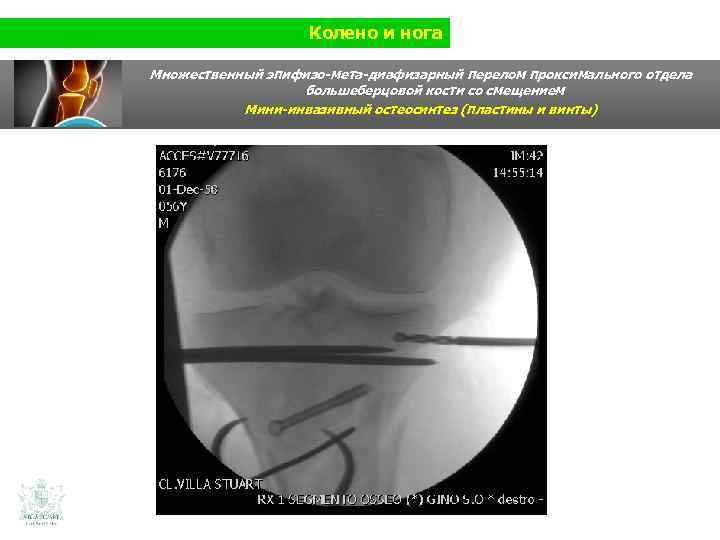

Колено и нога Клинический случай (колено и нога) Мужчина 56 лет Травма нижней конечности на мотоцикле Использования изображения в 3 D

Колено и нога Множественный эпифизо-мета-диафизарный перелом проксимального отдела большеберцовой кости со смещением

Колено и нога Множественный эпифизо-мета-диафизарный перелом проксимального отдела большеберцовой кости со смещением Изображение в 3 D (масштаб 1: 1) Использование изображения в 3 D способствует изучению перелома, его анализа в 3 хмерном измерении, для оптимальной подготовки к операции. Изображение в 3 D при сложных суставных переломах. Возожность реконструкции в 3 D позволяет изучить перелом. Настоящей революцией является то, что врач и пациент имеют возможность потрогать рукой пораженную часть кости во время исследования .

Колено и нога Множественный эпифизо-мета-диафизарный перелом проксимального отдела большеберцовой кости со смещением В 3 D во время операции Мы провели 20 операций по поводу перелома плато большеберцовой кости мини-инвазивным методом с использованеим модели в 3 D. Это позволило сократить время хирургической операции, рентгеноскопии и кровопотери по сравнению с операцией с применением остеосинеза миниинвазивным методом без модели в 3 D.

Колено и нога Множественный эпифизо-мета-диафизарный перелом проксимального отдела большеберцовой кости со смещением (Shatzer 6) Мини-инвазивный остеосинтез ( пластины и винты)